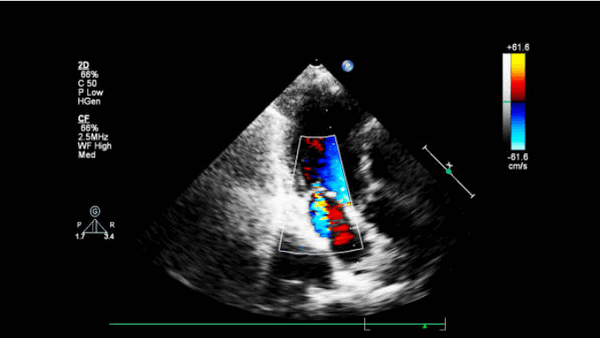

Анализ движения ближней стенки восходящего отдела грудной аорты проводится в режиме импульсно-волновой тканевой доплерографии с синхронной записью ЭКГ при задержке дыхания пациентом на протяжении 5-10 сердечных циклов. Контрольный объем размещается в области продольного среза восходящего отдела грудной аорты на участке на 3 см дистальнее фиброзного кольца аортального клапана при скорости развертки 50-100 мм/с. Точкой начала отсчета временных фаз считается первый антеградный систолический пик, соответствующий зубцу R ЭКГ. На каждом графике смещения доплеровских частот, отражающем скорости движения ближней стенки восходящего отдела грудной аорты, должны быть получены и выделены: S - скорость систолического смещения (см/с), А - скорость раннего диастолического смещения (см/с), E - скорость позднего диастолического смещения (см/с) (рис. 2).

Рис. 2. Левая парастернальная позиция по длинной оси на уровне 3 см выше аортального клапана, ИТД ближней стенки восходящего отдела аорты. S - скорость систолического смещения. Е - скорость раннего диастолического смещения. А - скорость позднего диастолического смещения